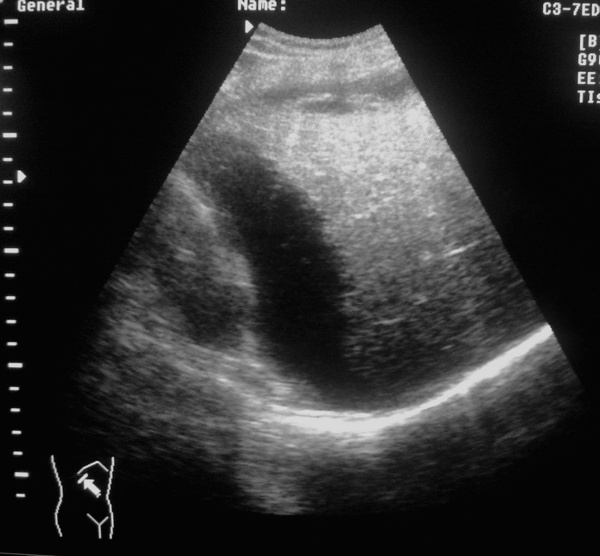

Мужчина,43года из пульмонологического отделения (в плановом порядке), жалобы на боли в области грудной клетки справа. Анамнез: травма в быту, упал с лестницы, ударился правой стороной (5-е сутки)

ОАК: Er 2.8 Hb 98 ц.п 0.88 Т 36,8 В анамнезе 2 года назад оперирован по поводу рака гортани.

ДЗ: Постравматическая н/долевая правосторонняя пневмония. З/перелом X-XI ребер справа. Анемия неясной этиологии.

Снимки 2-3 - не в брюшной ли полости жидкость?

Жидкости в брюшной полости не обнаружено. После УЗИ больной переведен в хирургическое отделение.

После Rtg пневмонию исключили.

Травма+анемия+ЭТО =?

Если маркеры стоят правильно, то это поддиафрагмальная внутрибрюшная гематома.

Возможно и внутрибрюшная, а может и подкапсульная гематома. Кстати, каковы критерии диф.диагноза?

Это по идее должно быть правой почкой. Между ней и печению - карман Моррисона - полость брюшины.